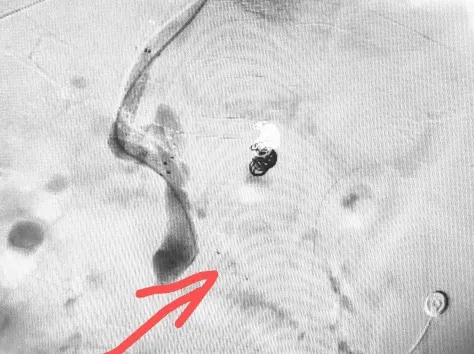

手术在局部浸润麻醉下有序开展,我院介入团队凭借丰富的临床经验和精准的操作技巧,通过特制穿刺装置成功完成肝实质穿刺,精准在肝静脉与门静脉之间建立分流通道,为后续治疗奠定基础。在关键的止血环节,团队创新性应用血管塞技术,对出血侧支血管进行精准栓塞(箭头所示为血管塞放置位置),栓塞效果立竿见影,成功阻断出血通路。